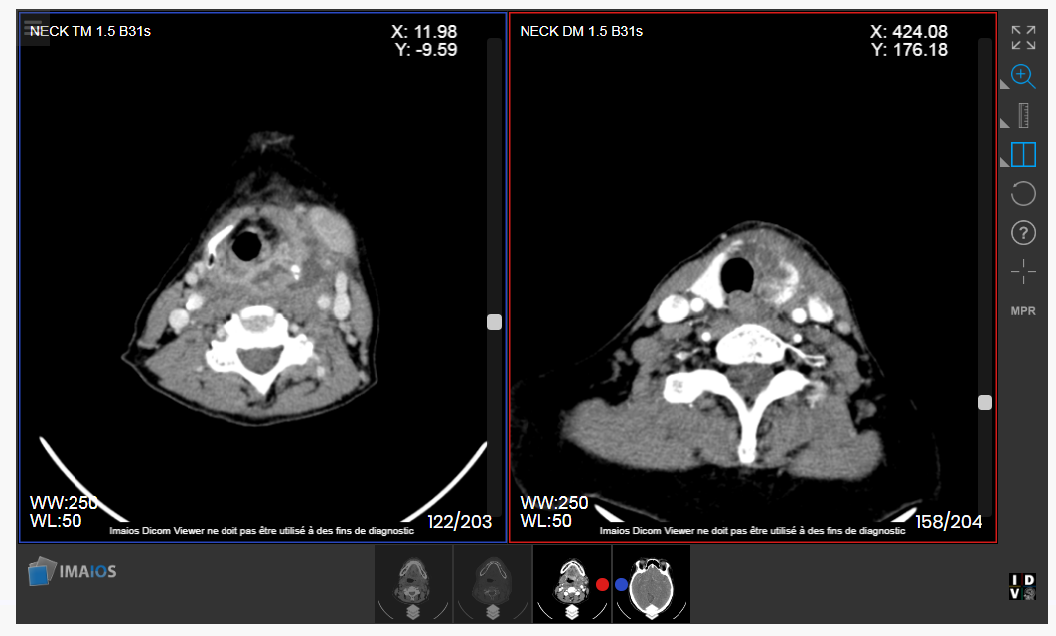

Chúng tôi mô tả một trường hợp bệnh cấp cứu đồng thời áp-xe tuyến giáp kèm nhiễm trùng cổ sâu ở khoang trước sống và khoang nguy hiểm. Bệnh nhân nữ Đ.T.N. Hương, 56t, có bệnh lý đái tháo đường không điều trị thường xuyên. Bệnh nhân không có tiền sử hóc xương, không có tiền sử bệnh lý tuyến giáp trước đó. Bệnh nhân có biểu hiện nuốt đau, kèm sưng nề vùng cổ, sờ thấy khối cứng, sẫm màu, không di động. Siêu âm vùng cổ cho kết quả vùng sau trên thùy giáp trái, trước thực quản có ổ tụ dịch nhiều hồi âm, giới hạn ít rõ, kích thước 23x30x51mm. Hình ảnh chụp cắt lớp vi tính cho thấy ổ áp-xe mô mềm lan rộng thành sau họng, kích thước 27 x 13mm, thâm nhiễm xung quanh. Bệnh nhân được tiến hành mổ cấp cứu dẫn lưu hai ổ áp-xe tránh gây biến chứng chèn ép đường thở và tránh gây nhiễm trùng lan tỏa vào trung thất, nguy hiểm đến tính mạng. Chẩn đoán vi khuẩn gây bệnh dựa vào kết quả lấy dịch mủ nuôi cấy, cho thấy nhiễm khuẩn Klebsiella pneumoniae có ESBL dương tính (men beta lactamase phổ rộng). Điều này có nghĩa vi khuẩn kháng lại rất nhiều các kháng sinh. Đây là gánh nặng thực sự trong điều trị nhiễm trùng trực khuẩn Gram âm, gia tăng chi phí điều trị do phải bắt buộc thay thế các kháng sinh cũ bằng các kháng sinh mới đắt tiền. Hiện tại, tình trạng nhiễm trùng và áp-xe được điều trị ổn định sau khi mở cạnh cổ dẫn lưu và điều trị phối hợp kháng sinh tích cực kèm súc rửa chăm sóc hố mổ hằng ngày.